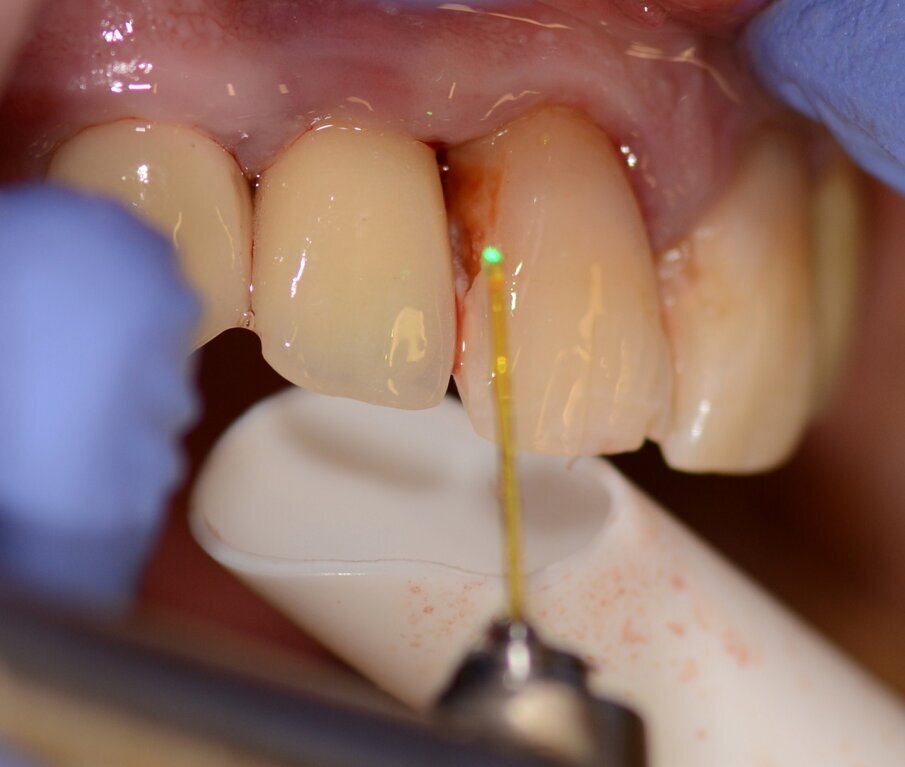

Of course, we can also use the Er:YAG laser for more common and “easy” procedures—like implant uncovering (Er:YAG). The healing is faster and we avoid suturing, but of course, even with the thin chisel tip, some amount of soft tissue is vapourised—so it cannot be conducted in all cases.

Figs. 4 & 5: Use of the Er:YAG laser Varian tip for granulation tissue removal, implant surface decontamination...

...and surface ablation of infected bone.

Fig. 16: Granulation tissue removal with Er:YAG.